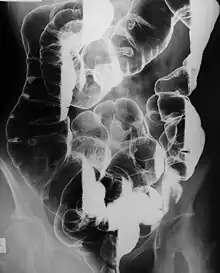

Peutz–Jeghers syndrome (often abbreviated PJS) is an autosomal dominant genetic disorder characterized by the development of benign hamartomatous polyps in the gastrointestinal tract and hyperpigmented macules on the lips and oral mucosa (melanosis).[2] This syndrome can be classed as one of various hereditary intestinal polyposis syndromes[3] and one of various hamartomatous polyposis syndromes.[4] It has an incidence of approximately 1 in 25,000 to 300,000 births.[5]

Complications associated with Peutz–Jeghers syndrome include obstruction and intussusception, which occur in up to 69 percent of patients, typically first between the ages of 6 and 18, though surveillance for them is controversial.[7][8] Anemia is also common due to gastrointestinal bleeding from the polyps.[8]

- Hamartomatous polyps in the gastrointestinal tract. These are benign polyps with an extraordinarily low potential for malignancy.

Resection of the polyps is required only if serious bleeding or intussusception occurs. Enterotomy is performed for removing large, single nodules. Short lengths of heavily involved intestinal segments can be resected. Colonoscopy can be used to snare the polyps if they are within reach.